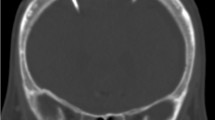

The Neurovent-P-tel sensor (Raumedic, Helmbrechts, Germany) is composed of a silicone-coated catheter (25 mm of length), whose tip contains a piezoelectric pressure sensor and its base, which hosts a disc-shaped data transducer. The base has to be positioned on the skull in the subcutaneous space (Fig. 1a). A radiofrequency transmission coil connected to a portable data recording device allows the acquisition of the ICP values. The pressure sensor is regularly inserted in the frontal lobe parenchyma. If placed in parallel to a shunt, it is positioned on the contralateral side of the ventricular catheter, thus measuring intraparenchymal pressure values. Implantation time should not exceed 90 days according to the company’s recommendations. The P-tel offers to measure pressure values with a detection rate from 1 up to 5 Hz.

Representative x-rays of the different set ups: a AP view on a Neurovent P-tel device on the left (*) and shunt system on the right with a proV-proSA-GA valve complex. b Lateral view on a Sensor Reservoir connected with proV-proSA-GA valve complex. In both the proSA was placed in between the two components of a proGAV valve. c Lateral view on a Sensor Reservoir as stand-alone device. proV programmable DP valve, proSA programmable shunt assistant, GA gravitational assistant unit, proGAV programmable DP valve with gravitational assistant unit

The Sensor Reservoir (SR, Miethke, Potsdam, Germany) is composed of a titanium-covered measuring cell hosted in a polyether-ether-ketone ring covered with a silicone membrane to allow puncture in order to withdraw CSF. The measuring unit contains a pressure sensor that directly transmits CSF pressure to the titanium cover and thus to the measuring unit. The device can be included in a shunt system and positioned on the burr hole, connected to a ventricular catheter proximally and a subcutaneous catheter laterally (Fig. 1b). To allow correct and reliable use of the device, the catheter position must be purely intraventricular to enable free flow of the water column toward the pressure cell, which was achieved to place the catheter correctly with a ventricular catheter guide [27]. The pressure values represent pressure measurements in the shunt system. The sensor is integrated in the CSF shunt system, which connects the intraventricular cavity with the peritoneal cavity regulated by the valve system distally located to the sensor. Measurements are allowed via a radiofrequency transmission antenna connected to a monitor. The manufacturer does not define an explantation time of the device. The device offers single measurements as well as high- and low-frequency measurements. The Sensor Reservoir offers to measure pressure values with a detection rate up to 44 Hz. This resolution of data acquisition was enabling to detect ICP waveforms during TICPM; however, detailed peak analysis of ICP pulsation could not be visualized.

The indication for telemetric ICP measurements for diagnostic purposes was unclear chronic clinical condition of suspected increased ICP elevation and possible candidates for CSF shunt treatment. In this context, in six patients, the Sensor Reservoir was used as “stand alone” solution in which a ventricular catheter was placed in the frontal horn of the lateral ventricle [27] connected to the Sensor Reservoir which was filled with CSF and was laterally occluded by a blind connector (Fig. 1c). This enabled not only the measurement of intraventricular pressure but also to diagnostically puncture the reservoir in order to detect pressure changes and possible clinical alterations after CSF volume relieve. This option was chosen in patients with unclear indication for a CSF diverting shunt in order to strengthen the decision for or against shunt implantation. Thereby, repeated lumbar punctures with unreliable single pressure detections were avoided (Fig. 2). Families or caretakers were informed about the risks and benefits of the different treatment options.